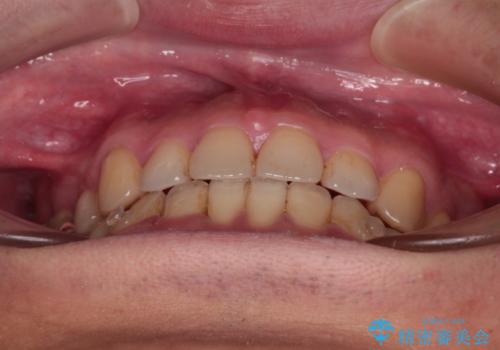

- 抜歯矯正の後戻りを気にして来院された患者様です。

舌の突出癖によるオープンバイトになり、前歯の叢生が後戻りしていました。

インビザラインの特性を活用して奥歯の咬み合わせを圧下させることで、前歯のオープンバイトを改善さえることができました。